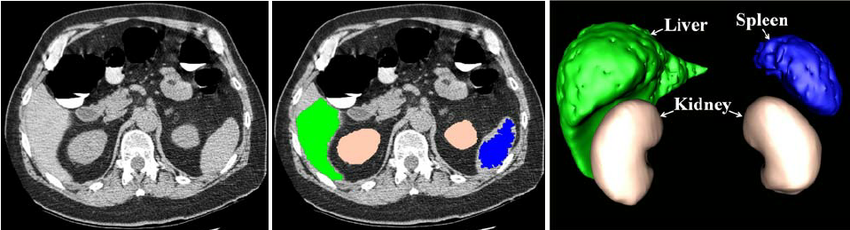

1.1.3 Computer vision: the machine learning algorithms

Segmentation of images is the process of partitioning the image into semantically meaningful parts and classifying each part into pre-determined classes. An example is depicted in Figure 1.2. As segmentation of medical images is a time consuming manual process, involving machine learning into this use-case has gained a high interest in the last years.

This model has already demonstrated good performance during a liver segmentation dedicated competition, and also its generality is demonstrated on different anatomical structures from the Visceral dataset.